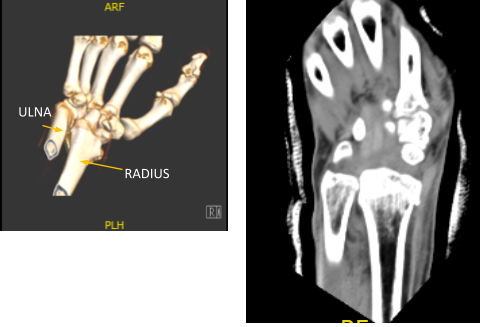

Xray were presented found comminuted impacted volarly angulated and volarly displaced intra-articular fracture of the distal radius. However, do not see any significant joint incongruity or step-off. There is ulnar plus variance. Minimally displaced fracture through the base of the ulna styloid. There is soft tissue swelling and joint effusion.

The anterior sheath was opened, the pronator quadratus was erased from its radial most margin. The fracture site was opened, manipulated and reduced and held with K-wires. Distal radial plate was put over the distal radius and fixed. be with olive wires.

C-arm images were taken and manipulated to be in the correct position. Finding The plate in appropriate position, fixation of the distal radius performed using locking and nonlocking screws distally and proximally.

After two weeks, the patient checked in with a presented Xray and saw that osseous and metallic elements are in good alignment. Patient is still in splint but not taking any pain medications. In 4th week’s post operation, observed plate fixing the distal radius is again noted with screws holding the plate in good position.